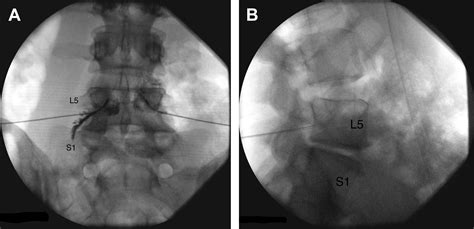

Accurate diagnosis of conditions affecting the lumbosacral transitional segment is essential for effective treatment. Several diagnostic methods are commonly used to evaluate this region:

• Imaging Studies: Imaging techniques such as X-rays, MRI, and CT scans are crucial for visualizing the anatomy of the lumbosacral region. These studies can reveal degenerative changes, herniated discs, spinal stenosis, and other abnormalities.